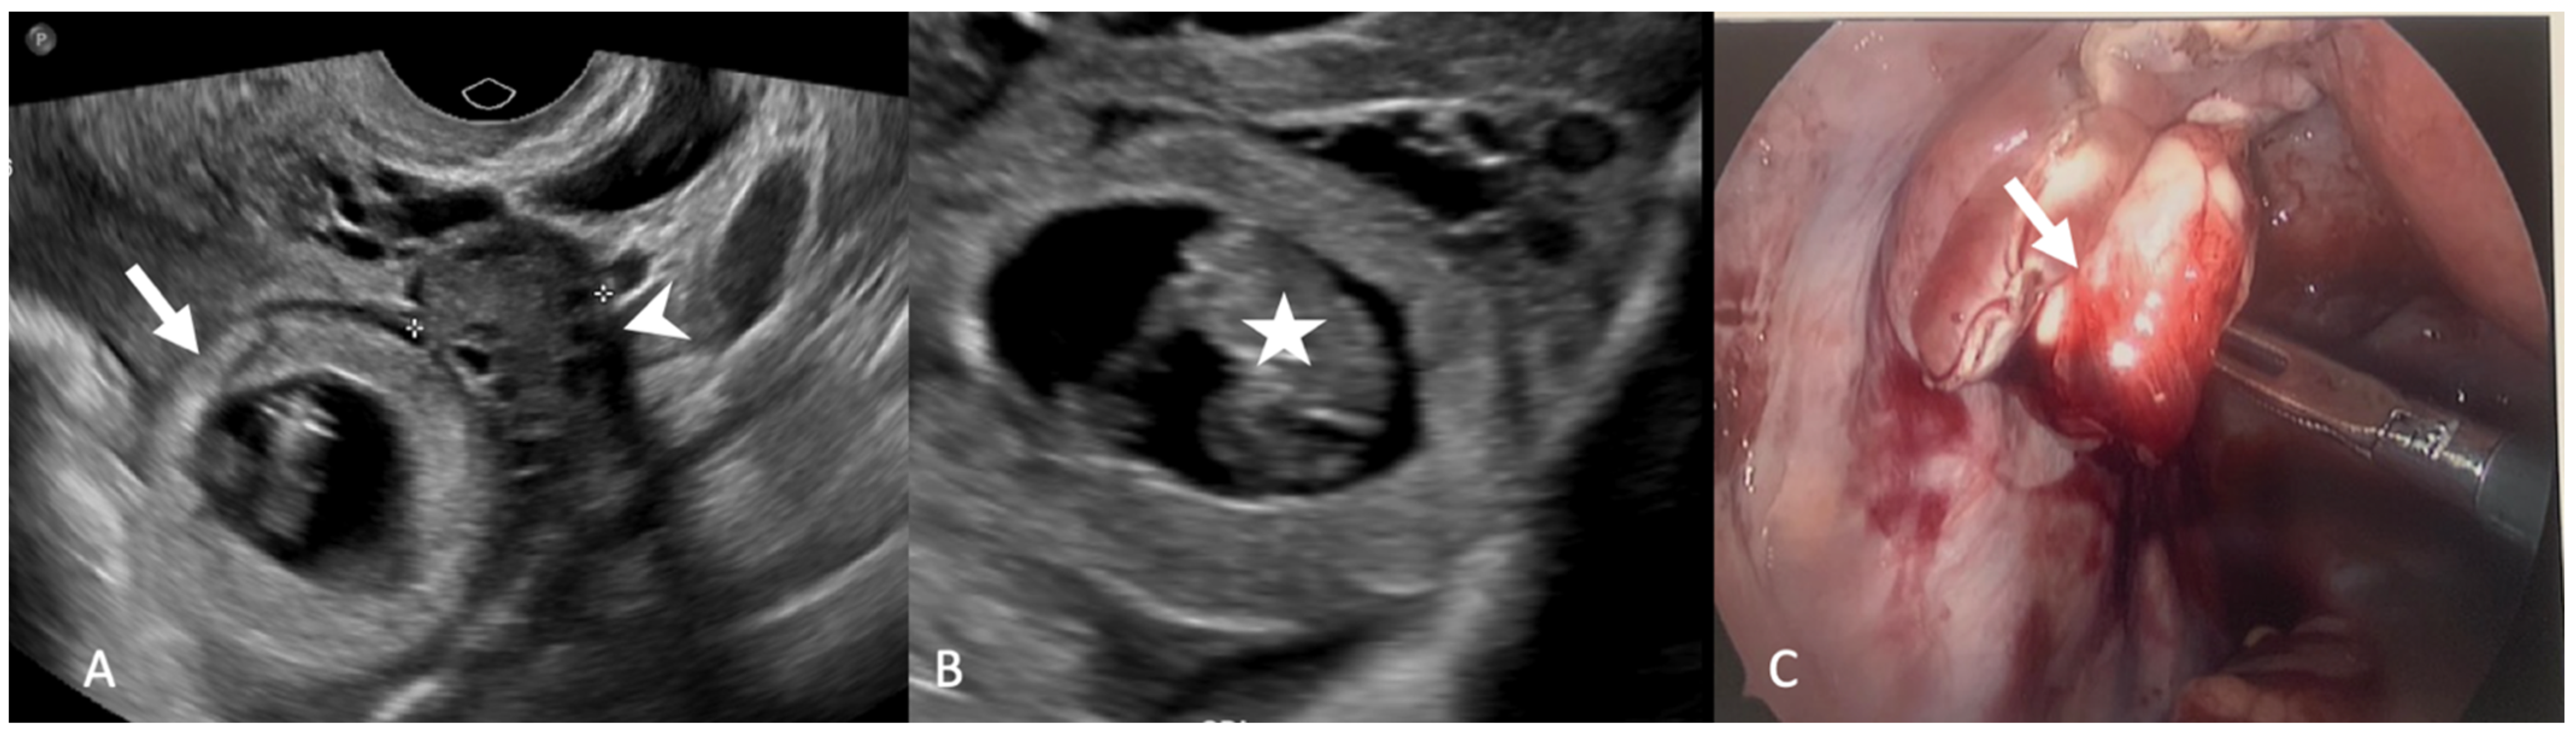

5.1.5. Paraovarian Cyst

5.1.6. Peritoneal Inclusion Cyst